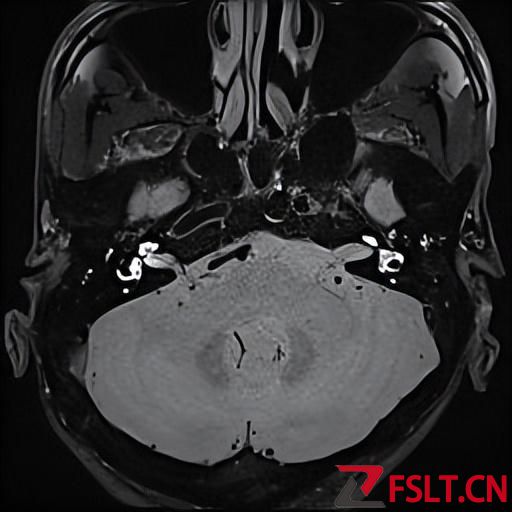

由于被这个病折磨的太久了,患者和家属决定还是做手术彻底治疗比较好。耳鼻喉梅晓峰主任和郑立岗主任带领手术团队认真分析患者的各项术前检查后一致认为患者梅尼埃病诊断明确,有反复发作,而且多次住院及长期药物治疗效果不佳,听力下降也非常严重,有内淋巴囊减压手术的适应症。

手术由梅晓峰主任和郑立岗主任主刀,这次做的是全麻内淋巴囊减压手术,在耳后做切口后暴露乳突骨皮质,打开乳突腔,暴露后半规管和内淋巴囊,切开内淋巴囊放置引流装置。缝合切口并放置负压引流。整个的手术用时约2个小时,非常顺利。术后第二天查房患者无明显的不适,无手术相关的并发症。自觉耳鸣消失,听力较术前稍有提高,无眩晕发作。